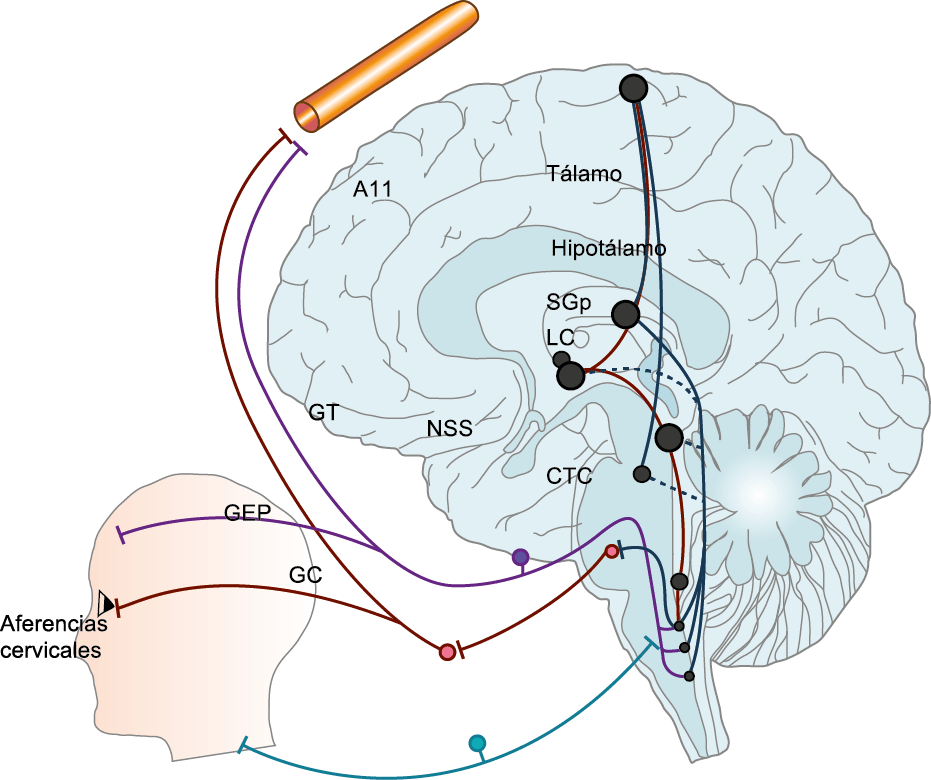

Todo lo mencionado contribuye al fenotipo del migrañoso y son vías que continuamente se están explorando para el desarrollo de nuevas terapias agudas y preventivas del dolor, más seguras y eficaces. Sin embargo, existe una controversia que gira en torno a dos cuestiones: la iniciación y el origen del dolor además de que todavía no se conoce el origen de los mecanismos neuronales que subyacen a la condición primaria en las personas susceptibles. Definitivamente la migraña implica la activación y sensibilización de las vías trigeminovasculares, así como el tronco cerebral y los núcleos diencefálicos(88). La vía aferente comienza en las aferentes vasculares nociceptivas de la duramadre que están para advertir, no para localizar. Su proyección al tálamo y la corteza y como se regula esta vía en cada nivel y por múltiples sistemas, ofrece la posibilidad de comprender los síntomas complejos y orientar las terapias. Los ataques comienzan como síntomas premonitorios, dificultad para concentrarse, bostezos, fluctuaciones del humor; y cambios homeostáticos, como la alimentación y el equilibrio de líquidos, que pueden incluir sensibilidades más generalizadas, como fotofobia y fonofobia. La fase premonitoria da paso a la fase de dolor con el sufrimiento acompañante y termina en una fase posdrómica de sentirse agotado por la experiencia. (Figura 1)

Un principio importante de esta teoría es que el desencadenante principal de la migraña proviene de la periferia, en los vasos sanguíneos de la duramadre, con la activación del sistema trigeminovascular proveniente del disparo de las neuronas trigeminales periféricas de primer orden en respuesta a una lesión nociceptiva o señales provenientes de las meninges que liberan mediadores neuroinflamatorios. La activación sostenida de las neuronas nociceptivas meníngeas durales provoca la activación secuencial y la sensibilización de las neuronas trigeminovasculares de primer orden (nociceptores periféricos), segundo orden (a nivel del TCC-complejo trigémino cervical) y tercer orden (trigeminotalámico), (Figura 5) así como la activación ascendente del cerebro, tallo y otras estructuras diencefálicas(97).

El dolor de la migraña es, sin duda, una consecuencia de la activación o la percepción de la activación de los mecanismos neurovasculares, de allí que sea considerado un trastorno puramente neuronal. Mucha evidencia indica que los cerebros de las personas con migraña pueden ser diferentes en la forma en la cual responden a la estimulación sensorial, incluso interictalmente(102). Una hipótesis alternativa y que lo abarca todo es que el cerebro está en el centro del desencadenamiento de la migraña. Más que una activación secuencial de diferentes regiones del cerebro, la migraña es un trastorno del cerebro y por lo tanto, se considera un “estado cerebral”, que es una consecuencia de cambios o disfunciones en las regiones del tronco encefálico y el hipotálamo, que contribuyen a su vez a cambios a nivel celular y vascular en muchas regiones del cerebro. Esta hipótesis establece que la migraña puede describirse mejor como una consecuencia de la disfunción en el tronco encefálico y los núcleos hipotalámicos que normalmente modulan o activan las entradas sensoriales, como el tacto, la luz, los sonidos y los olores. Estos núcleos del tronco encefálico y del hipotálamo pueden considerarse “mediadores de la migraña” y su disfunción puede llevar al fracaso de los mecanismos de integración y filtrado cerebrales, lo que da como resultado la percepción de activación de los sistemas sensoriales en condiciones normales. La compleja red de conexiones entre las regiones del tronco encefálico, que incluyen PAG, RVM, locus ceruleus y SuS y los núcleos diencefálicos, incluidos el hipotálamo, el tálamo y la corteza, pueden conducir a la generación de síntomas a través de la misma disfunción central. La disfunción en estas regiones, a través del control descendente del tráfico nociceptivo trigeminovascular, puede conducir a la percepción del dolor de cabeza a través de la palpitación de los vasos normales y la disfunción continua puede conducir a la sensibilización central de las neuronas trigeminovasculares y la exacerbación del dolor con la actividad física normal, así como en la piel: alodinia cefálica y extracefálica. La convergencia de entradas sensoriales en el tálamo que se proyectan a la corteza puede explicar la hipersensibilidad a la luz, los sonidos y los olores. La misma disfunción puede conducir a cambios homeostáticos, controlados por el hipotálamo, relacionados con el sueño, la alimentación y la actividad. La alteración general de la función cortical y subcortical puede desencadenar eventos como el aura migrañosa y extenderse a una incapacidad general para funcionar correctamente. Los factores genéticos heredados juegan claramente un papel en la predisposición a la susceptibilidad a la migraña, al igual que el papel de los desencadenantes potenciales de la migraña, cuyo vínculo común parece jugar en el corazón de la homeostasis cerebral en el hipotálamo y el tronco encefálico. (figura 7).

El dolor de cabeza asociado con un ataque de migraña, puede incluir la región frontal, temporal, parietal, occipital y cervical alta, es consecuencia de la activación del sistema trigeminovascular. (Figura 10)

Hay una proyección aferente central desde el ganglio del trigémino que ingresa a la médula caudal del tronco encefálico, a través del tracto del trigémino, que termina en el núcleo espinal del trigémino caudalis (TNC), así como la médula espinal cervical superior (C1–C2). (Figura 16)

Las fibras nociceptivas Aδ y C terminan predominantemente en las láminas superficiales, I y IIo, así como en las láminas más profundas V–VI del TNC y extensión cervical. La estimulación de la vasculatura dural en modelos animales, incluidos los senos transverso y sagital superior y la arteria meníngea media, da como resultado la activación de las neuronas en las regiones TNC, C1 y C2 de la médula espinal cervical, conocidas en conjunto como el complejo trigeminocervical (TCC).

Estos datos sugieren que el núcleo del trigémino se extiende hasta el asta dorsal de la región cervical superior en un continuo funcional que incluye la extensión cervical, ello explica la distribución de la percepción del dolor en la migraña sobre las regiones frontal y temporal, además de la participación de parietal, occipital y regiones cervicales superiores(27).

Por lo tanto, se cree que la naturaleza intensa y pulsátil del dolor en la migraña es el resultado de la activación, o la percepción de activación, de estas entradas nociceptivas de las estructuras intracraneales y extracraneales, que convergen y se transmiten a través del TCC. (Figura 17)

Toda la información nociceptiva de las estructuras craneovasculares se transmite a través del TCC y mediante conexiones ascendentes a otras áreas del tronco encefálico y el diencéfalo, involucradas en el procesamiento del dolor y otra información sensorial. La activación de la vía antes mencionada contribuye a la percepción del dolor durante la migraña y también a los síntomas autonómicos, endocrinos, cognitivos y afectivos que duran todo el episodio migrañoso.

El procesamiento del dolor es complejo y está mediado por una red de estructuras neuronales que incluyen la corteza cingulada, las ínsulas y el tálamo(28). El tálamo está en el corazón del procesamiento central y la integración de la información nociceptiva y se considera un centro de retransmisión para manejar la información sensorial entrante e incluso modularla. Se cree que la llamada “matriz del dolor”, que incluye el tálamo, así como las áreas somatosensoriales primarias (S1) y secundarias (S2), la corteza cingulada anterior (CCA) y la corteza prefrontal, está involucrada en la integración de todos los sentidos, respuestas afectivas y cognitivas al dolor y se activan durante el procesamiento nociceptivo(28). (Figura 18)

Siendo el tálamo el centro principal para el procesamiento de la información nociceptiva sensorial en el cerebro, la transmisión de esta información para su procesamiento en las estructuras corticales donde los individuos la perciben es un factor clave. (Figura 18) Los tratamientos agudos como los “triptanos” (agonistas de los receptores 5-HT1B/1D)(29) y los antagonistas de los receptores CGRP(30) pueden inhibir las entradas nociceptivas durales agudas. Del mismo modo, los preventivos de la migraña propranolol(31), valproato de sodio(32) y topiramato(33)también pueden inhibir las entradas trigeminotalámicas nociceptivas durales en el VPM (Núcleo ventral posteromedial).